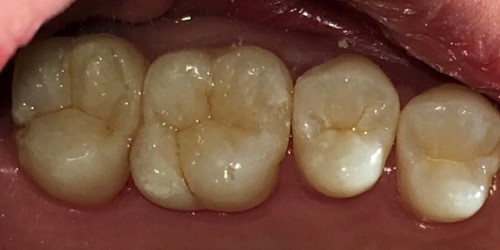

CASE03ダイレクトボンディング

Before

After

| 主訴 | できるだけ歯を削らずに銀歯を白くしたい。 |

|---|---|

| 治療方法 | 銀歯を除去した後、ダイレクトボンディング法によりコンポジットレジンを用いて修復した。 |

| 治療期間 | 1回 |

| リスク | 長年使用することによる着色。咬合圧が強い場合破折することがある。 |

| 費用 | 55,000円×2(税込み) |